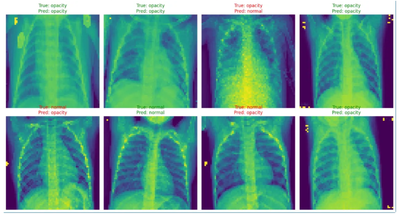

Here is how to trained a lightweight Convolutional Neuronal Network (CNN) to detect pneumonia from chest X-rays pictures on Azure Databricks.

1. Built it with TensorFlow & Keras on Databricks

2. Dataset: 4,000+ chest X-rays labeled as normal or pneumonia. Source - Kaggle

3. It doesn't hallucinate โ it predicts, with a confusion matrix available